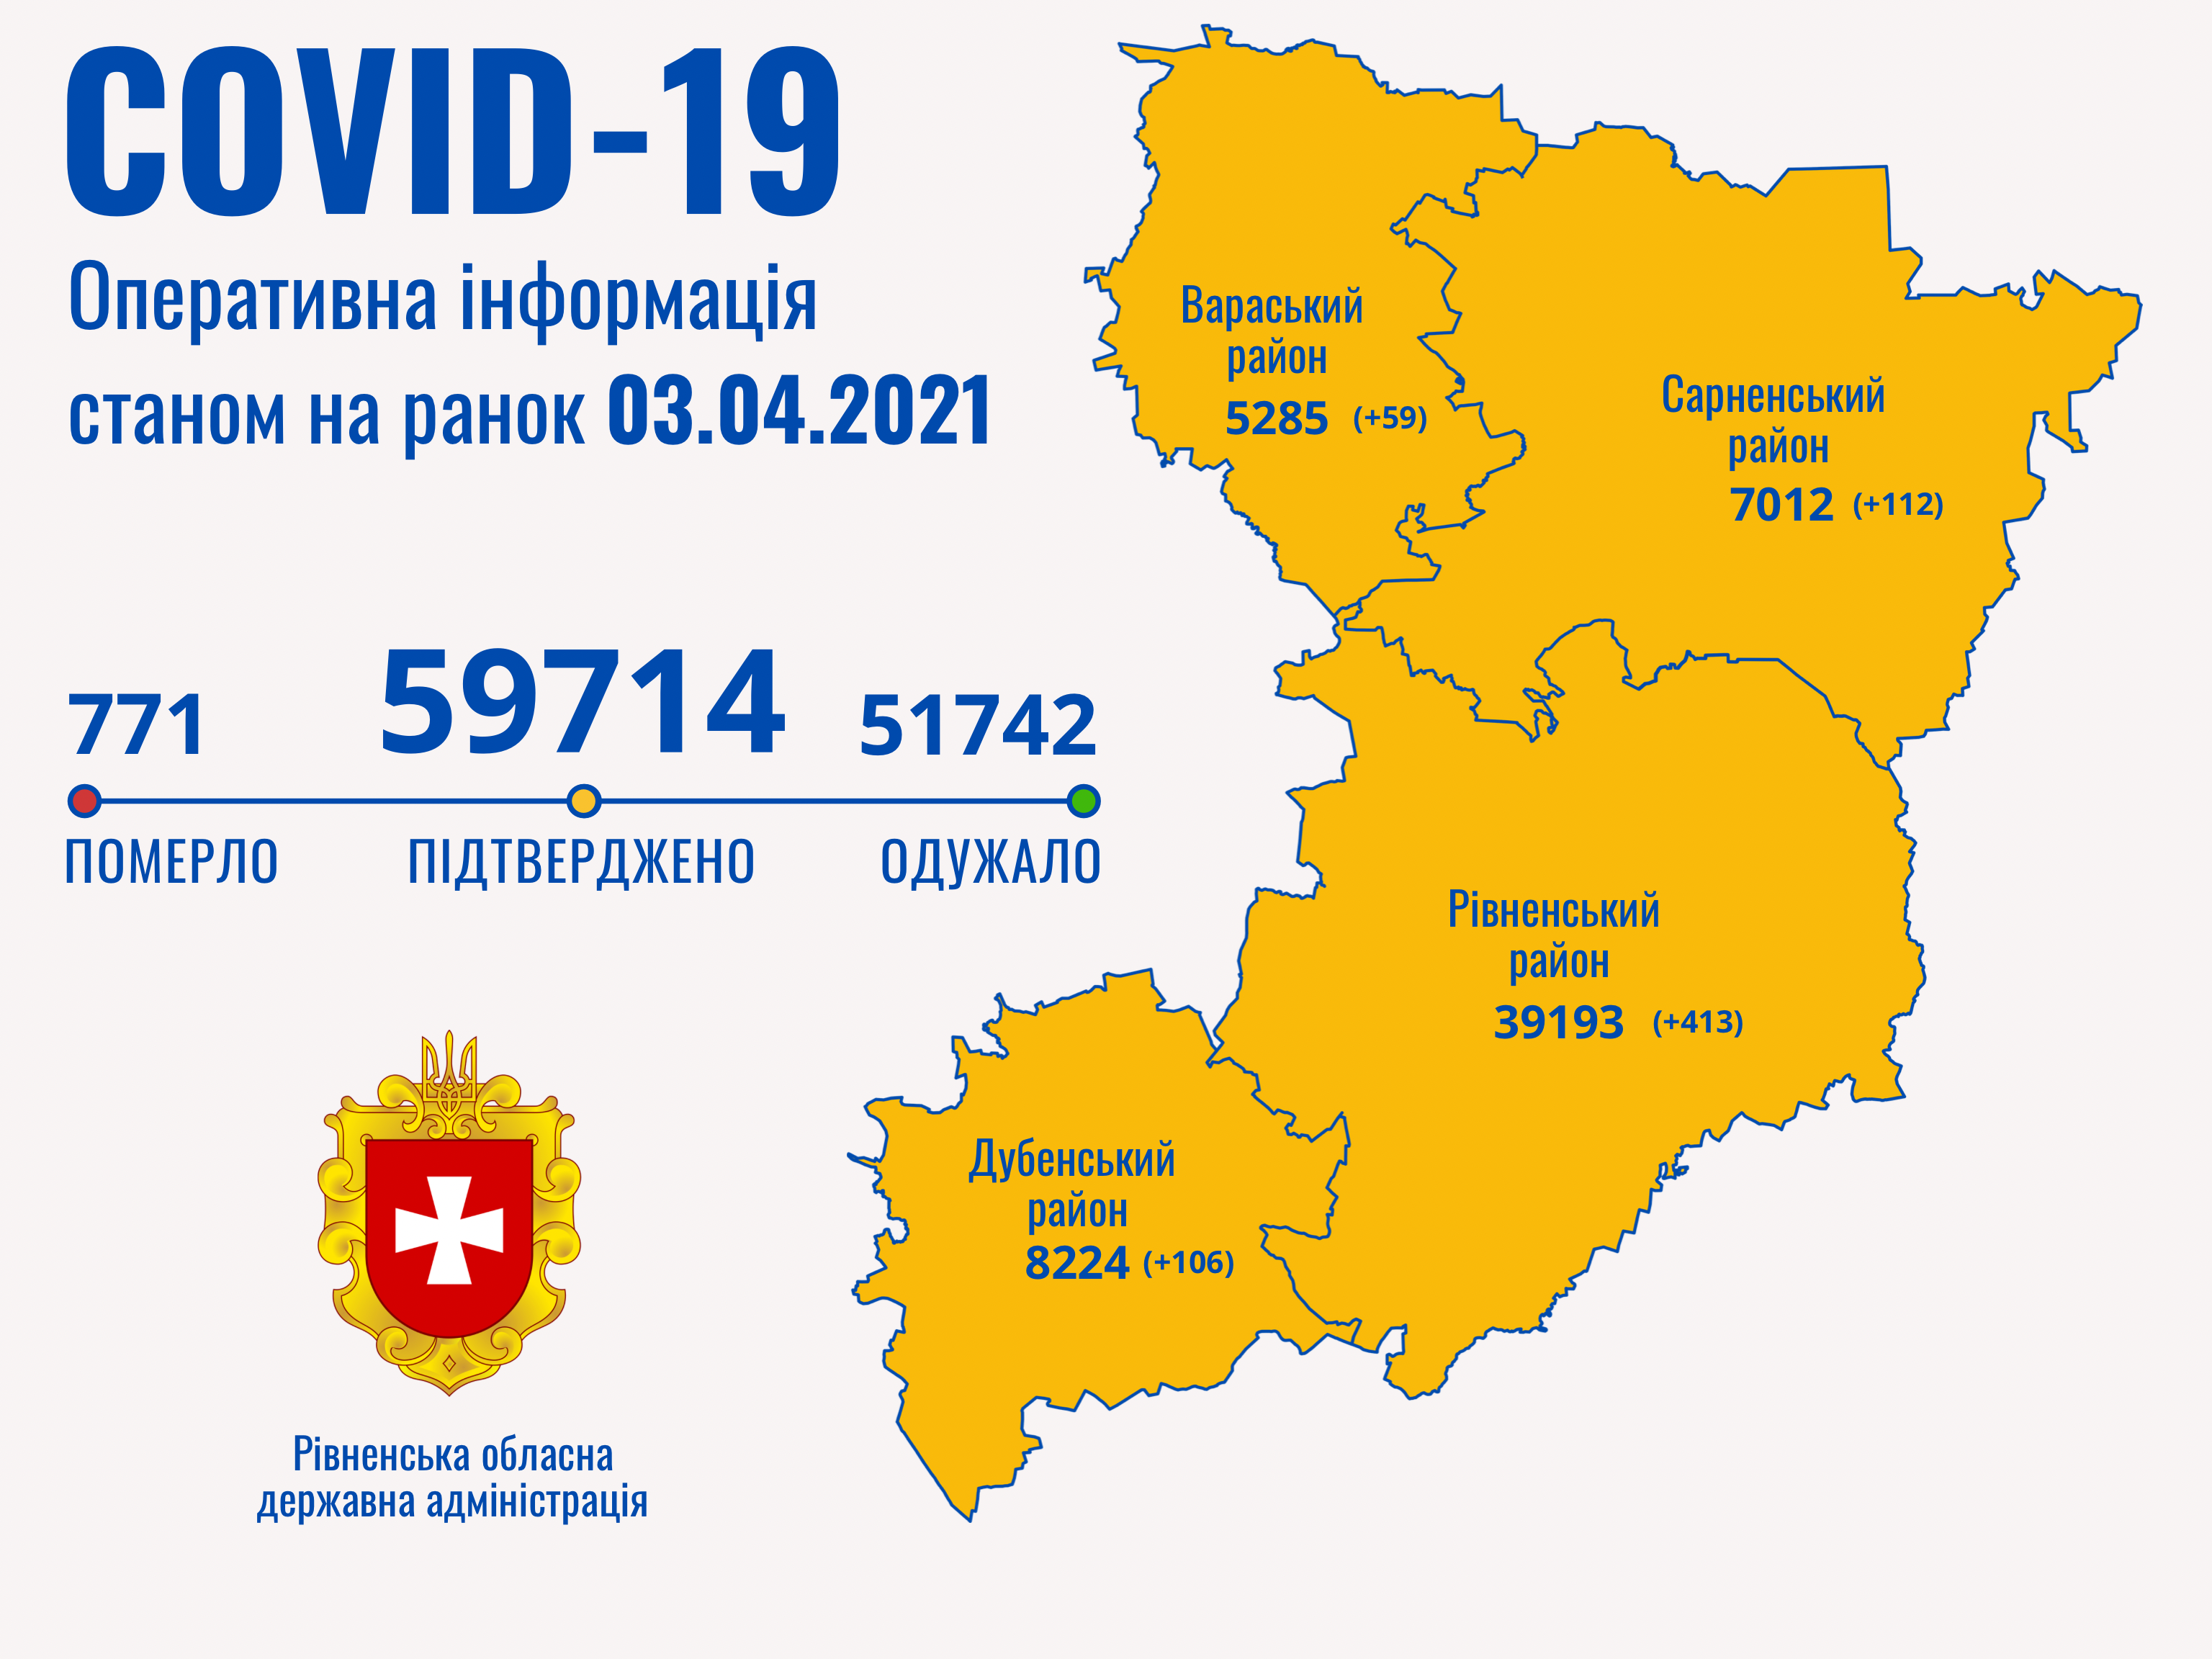

Пів тисячі - у важкому стані, 9 жителів Рівненщини померли за добу від коронавірусу

12.04.2021 10:17